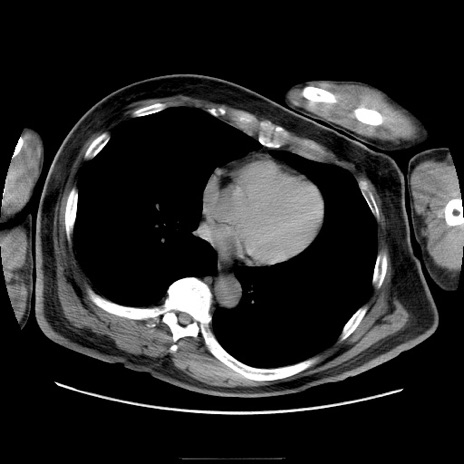

症例22(横断像)

【症例】50歳代男性

【主訴】腹痛

【現病歴】AVMからの被殻出血のため回復期リハ病棟入院中。 本日午後3時頃急に下腹部痛が出現した。

【既往歴】AVM、被殻出血、虫垂炎、高血圧

【身体所見】意識晴明、左半身不全麻痺、会話の理解は良好、36.5°C、腹部:膨隆、全体に板状硬、下腹部正中に圧痛点あり、反跳痛-、筋性防御不明、右下腹部にope scar

【データ】WBC 9400、CRP 0.06